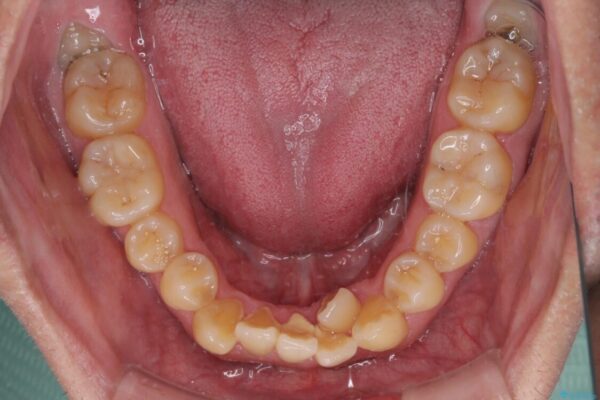

八重歯と前歯のクロスバイトを改善したいとのことで来院された患者様です。

デコボコの程度は強かったのですが、口元の突出感はなかったため、非抜歯矯正としました。

治療前

• 八重歯とクロスバイト 目立たないワイヤー装置で矯正治療 治療前画像